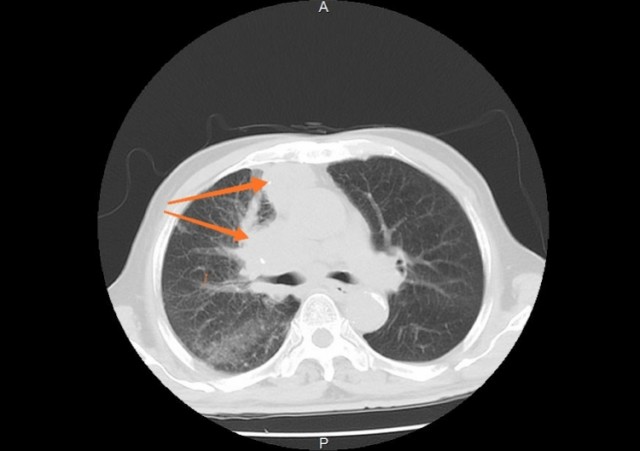

肺肿瘤x光片图,肺肿瘤CT图片

肺肿瘤CT图片

肺肿瘤ct图片表现

肺肿瘤ct影像图片

肺肿瘤长什么样图片

肺肿瘤ct

肺肿瘤是什么样子图片